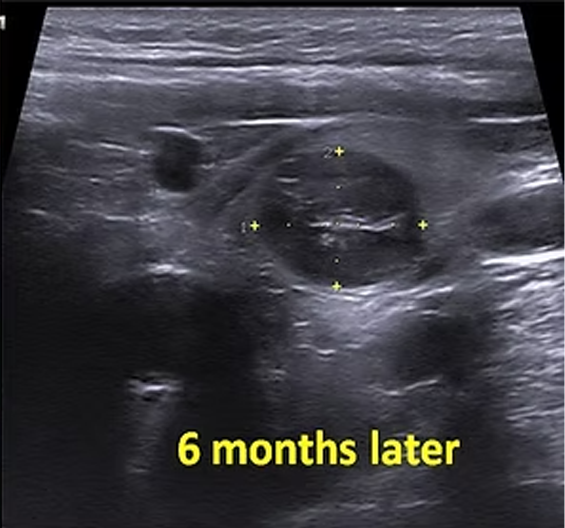

A 31 year old male with a 10cm benign solid nodule in the left thyroid lobe underwent embolization. Six months later, the volume of the nodule decreased by 90% and the appearance of the neck was practically normal.